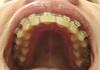

А это дуги. Нижняя для меня вообще фантастика. А верхняя.. ну верхняя очевидно кривая, все-таки врожденная адентия сказывается и на кости. Я пока не спрашивала, если честно, насколько получится скорректировать тут.

Волна большая, но была еще сильнее. У меня фото-зуд с апреля только начался, а начальные (февральские до установки) только у доктора есть.